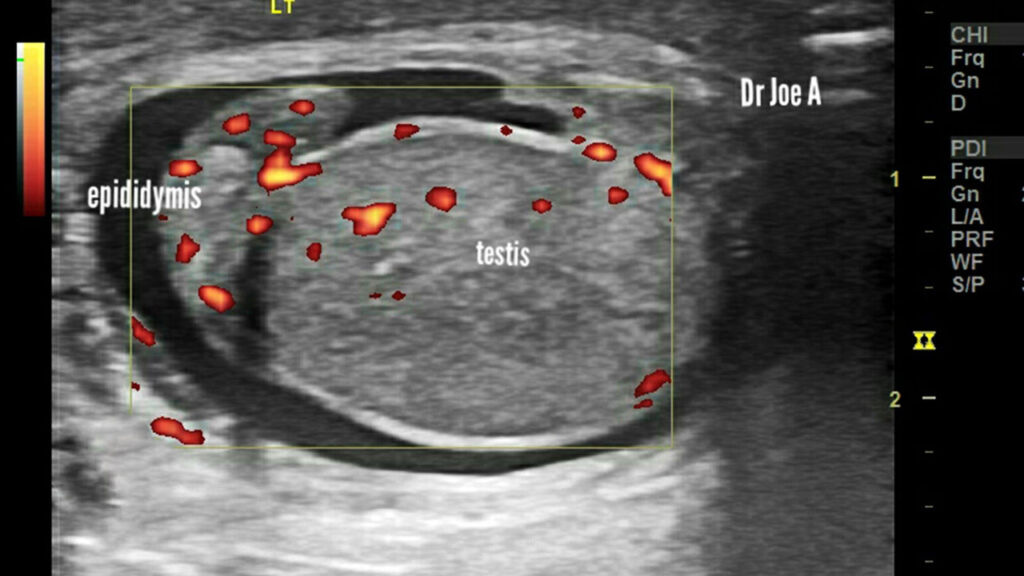

آپاندیس بیضه یک زائده کوچک متشکل از بافت طبیعی است که معمولا در قسمت فوقانی بیضه قرار داشته و آپاندیس اپیدیدیم زائده کوچکی در بالای اپیدیدیم (ساختاری لوله ای شکل متصل به بیضه) است.